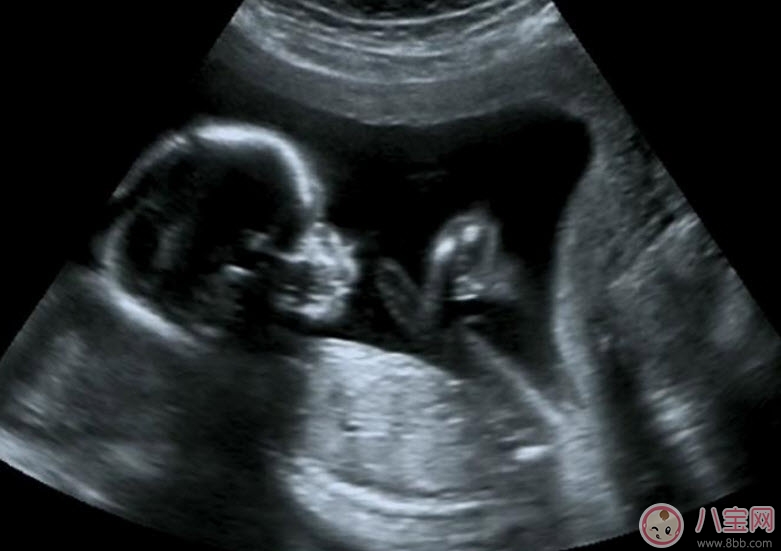

B超既可以測量胎兒的各個部位,如胎頭大小、胎臀長度,也可以用于在早期妊娠來測定胎兒的具體懷孕時間(醫(yī)學上叫做孕周),測定胎頭的雙頂徑、頭圍、腹圍及胎兒股骨的長度等,這些數(shù)據(jù)可以判斷胎兒的生長發(fā)育情況。

B超能夠直觀胎兒在母體內(nèi)的活動狀況,諸如呼吸情況、胎兒的運動、整個身體大的運動、肢體的運動、胎兒的吞咽動作等等,可以一覽無余。之外,通過觀察胎兒的張力是否良好,可以判斷胎兒在宮內(nèi)是否缺氧或者受到損害,準確預報胎兒安危。